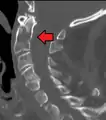

A fracture of the base of the dens as seen on CT

Type 3 odontoid fracture